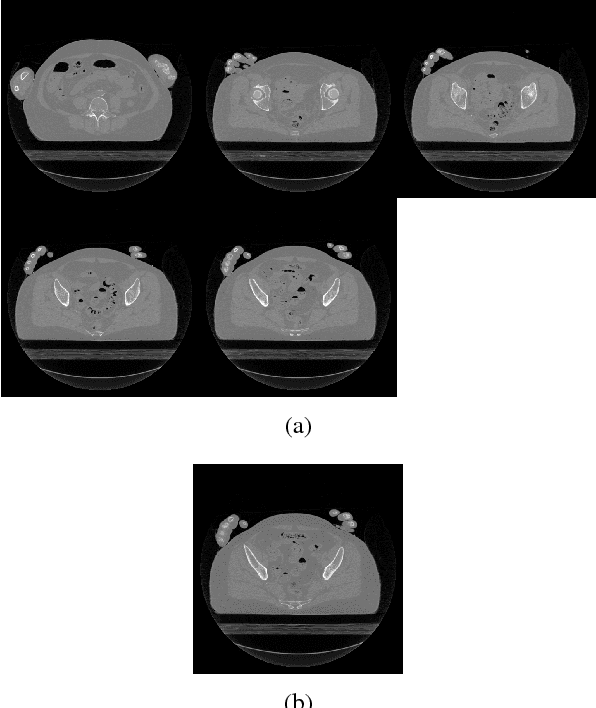

Abstract:Recent research in tomographic reconstruction is motivated by the need to efficiently recover detailed anatomy from limited measurements. One of the ways to compensate for the increasingly sparse sets of measurements is to exploit the information from templates, i.e., prior data available in the form of already reconstructed, structurally similar images. Towards this, previous work has exploited using a set of global and patch based dictionary priors. In this paper, we propose a global prior to improve both the speed and quality of tomographic reconstruction within a Compressive Sensing framework. We choose a set of potential representative 2D images referred to as templates, to build an eigenspace; this is subsequently used to guide the iterative reconstruction of a similar slice from sparse acquisition data. Our experiments across a diverse range of datasets show that reconstruction using an appropriate global prior, apart from being faster, gives a much lower reconstruction error when compared to the state of the art.